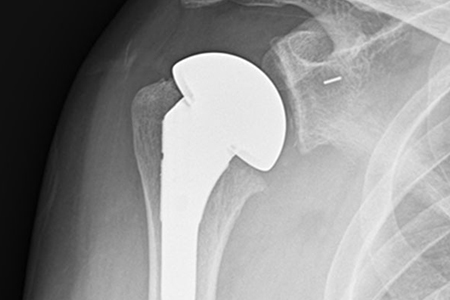

초기에는 약물치료를 할 수 있으나 고령이면서 통증이 잘 조절되지 않고 가성마비가 생긴 경우 인공관절 치환술을 통해 회복할 수 있습니다.

어깨부위 방사선(X-ray) 검사를 통해 관절염 여부를 확인할 수

있습니다. 검사상 어깨 뼈 사이가 좁아지거나 비정상적인 골극이

생성되어 관절면이 불규칙적이며 굳어있는 것이 관찰됩니다.

CT와 MRI 정밀검사를 통해 어깨 관절 변형 정도를 정확하게

파악해 볼 수도 있습니다.